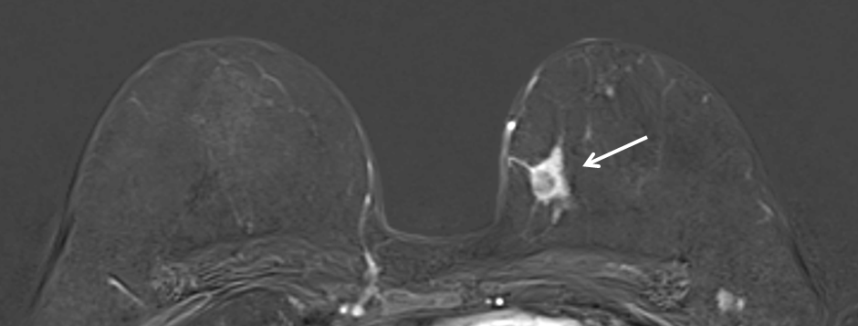

Kernspinuntersuchung einer 55jährigen Patientin mit gesichertem Karzinom in der linken Brust (im Bild rechts, Pfeil)

Die Kernspinuntersuchung der Brust ist nicht generell für die alleinige Brustkrebsfrüherkennung geeignet und kann auch nicht die Mammographie oder die Sonographie ersetzen.